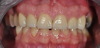

Eclaircissement et couronnes céramo-céramiques

Couronnes céramiques sur incisives latérales et facettes sur incisives centrales